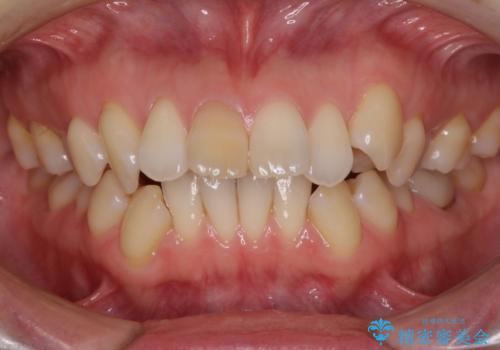

- 上の前歯の飛び出した感じを改善したいとのことで来院された患者様です。

上顎左右第一小臼歯2本、下顎左右第二小臼歯2本を抜歯し、ワイヤー装置にて口元を引っ込めるよう矯正治療を行うこととしました。

上下の前歯に隙間が空くほど上顎前歯が前に飛び出していましたが、抜歯矯正により上下前歯がぴったりと付くほど口元を引っ込めることができました。